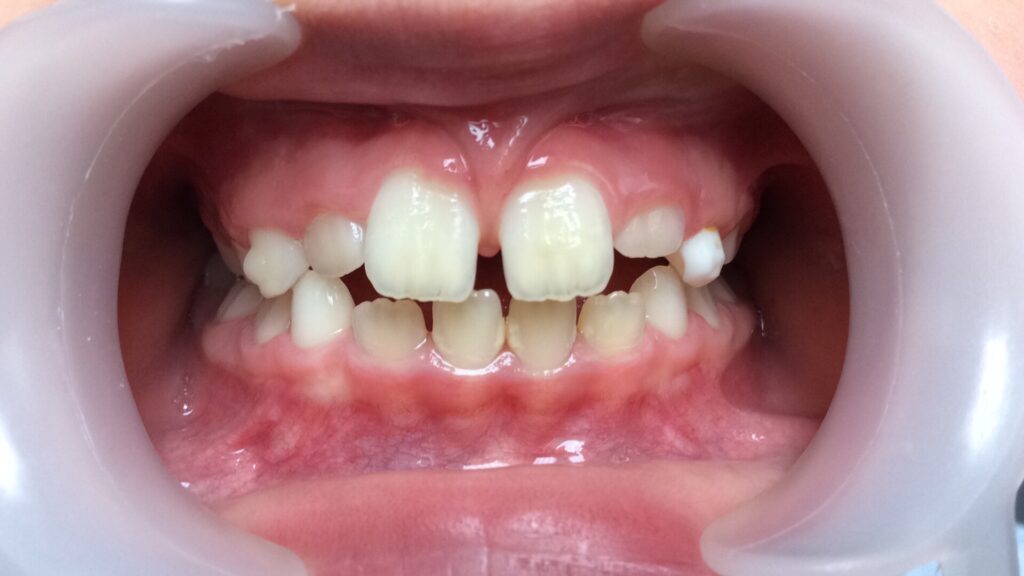

Un cas de béance :

6 mois de traitement et une élocution nettement améliorée

Traitement débuté à 3,5 ans et terminé à 4 ans